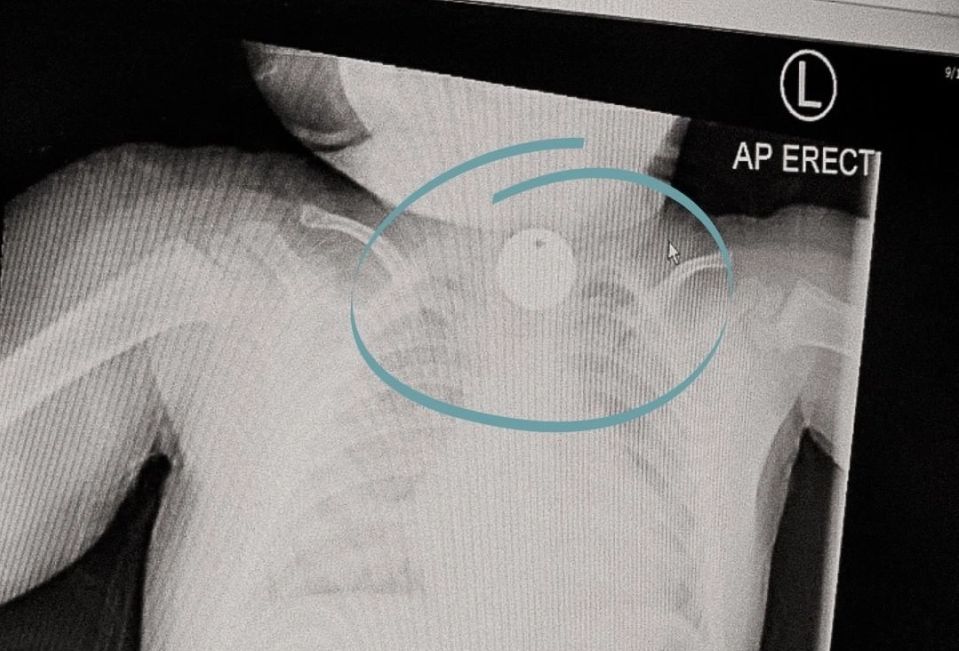

Do takich sytuacji niestety dochodzi często, a najlepszym tego dowodem jest tablica w Górnośląskim Centrum Zdrowia Dziecka. Zdjęciem gabloty, wywieszonej na korytarzu, podzieliła się na Instagramie psycholożka Agata Głyda.

Na magnetycznej tablicy lekarze pokazali, co udało im się wyjąć z przewodów pokarmowych dzieci. Niebezpiecznych przedmiotów jest cała masa: od magnesów po klucze. Wszystkie przedstawione przedmioty są nam doskonale znane. Każdy ma je w domu i pewnie nie jedno dziecko ma do niej dostęp.

Głyda kilka lat temu doświadczyła na własnej skórze, jak wygląda walka o życie dziecka, które połknęło baterię. Na szczęście kobieta szybko zareagowała i skończyło się na niewielkiej bliźnie przełyku.

Tablicę w swoich social mediach pokazała ku przestrodze. "Może w ten sposób uda się uchronić kolejne dzieci przed stresem, bólem i trudnym wspomnieniem do końca życia?" - napisała.